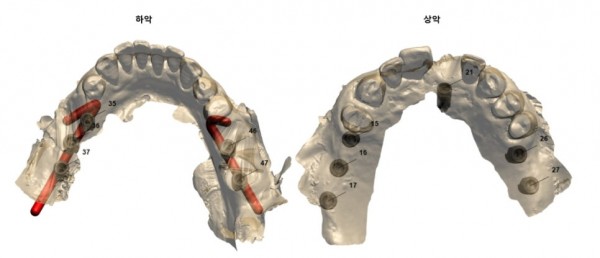

이때 임플란트 위치 선정과 각도 조절을 위해

사전에 디지털장비를 이용해 계획했는데요.

이러한 작업을 통해 수술 시간도 단축되고

환자분의 부담도 줄일 수 있습니다.